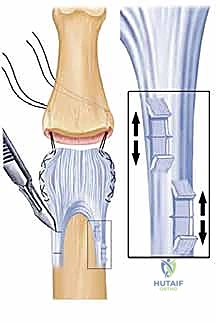

المبدأ العلمي للعملية

عندما تنكسر قاعدة السلامية الوسطى (من الجهة السفلية)، يفقد المفصل "الشفة" التي تمنعه من الانزلاق للخلف. في عملية VPA، يقوم الدكتور هطيف بإزالة القطع العظمية المكسورة والمتفتتة. ثم يقوم بفك وتحرير الصفيحة الراحية السليمة، ويسحبها إلى داخل عيب العظم (المكان الذي تمت إزالة العظم منه). يتم تثبيت هذه الصفيحة بقوة في العظم.

النتيجة؟

1. الصفيحة الراحية تعمل كسطح مفصلي ناعم بديل للعظم المكسور.

2. الشد الناتج عن تثبيت الصفيحة يعمل كحاجز ميكانيكي قوي يمنع المفصل من الانزلاق للخلف (يمنع الخلع الظهري).

الخطوة 4: تحضير العظم وتشكيل الخندق

يتم تحديد القطعة العظمية المكسورة في قاعدة السلامية الوسطى وإزالتها. باستخدام أدوات دقيقة جداً، يقوم الدكتور هطيف بحفر "خندق" صغير أو تجويف في قاعدة العظمة، ليكون هو السرير الذي ستستقر فيه الصفيحة الراحية.

الخطوة 5: تقديم وتثبيت الصفيحة الراحية

يتم تمرير خيوط جراحية قوية جداً (أو استخدام خطاطيف عظمية حديثة - Bone Anchors) في الحافة الحرة للصفيحة الراحية. يتم سحب هذه الخيوط من خلال ثقوب دقيقة تم حفرها في السلامية الوسطى، لتخرج من الجهة الظهرية (العلوية) للإصبع. عند شد هذه الخيوط، تُسحب الصفيحة الراحية بقوة وتستقر داخل "الخندق" العظمي. يتم ربط الخيوط فوق زر بلاستيكي صغير على ظهر الإصبع لتثبيتها (Pull-out Suture Technique).